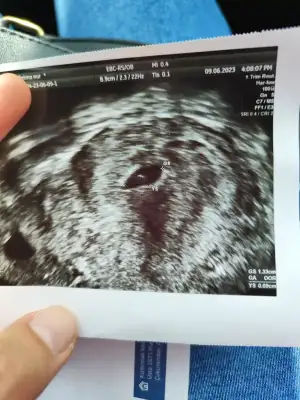

Kızlar doktordan çıktım yolk ve keseyi gördük çok şükür kalp atışı için 10 gün sonra gel garanti olsun dedi istanbuldaki doktoruma gidecegim inşaallah. Mindamin Mindamin senin dediğin gibi yaptı hesabı 5 buçuk haftalık sesi transferin üstüne 12 gün ekledi 😀

Ne güzel bir görüntü bu maşallah bebişe😍 hadi sırada kalp atışı var dünyanın en güzel sesi❤ tüp bebek hesabı her yerde öyledir ama internet siteleri farklı yapıyor kafa karıştırıyorlar 🤷‍♀️